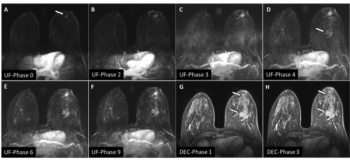

Figure 1. A: Original image. B: Filtered image. C: Normalized image overlaid with left and right individual thalamus regions. Figure 2. Mean and 95% confidence interval of thalamic volumes relative to control subjects (bars) and relative to the patient (points). The volume of the left thalamus was 3.89 cm3 while right thalamus was 3.71 cm3. The values of matched healthy control subjects were 4.58 cm3 ± 0.26 cm3 for the left thalamus and 4.10 cm3 ± 0.23 cm3 for the right thalamus. All volumes were calculated accounting for total intracranial volume.

These results confirm previous findings in thalamic volumetry of patients with schizophrenia. By studying a patient with a specific symptom (persistent auditory hallucinations), it is possible to relate the effect of this phenotype in a specific finding to decreased thalamic volume.

As demonstrated in previous studies,5 significant correlation can be observed between PSYRATS/BPRS variables and gray matter volume when evaluating schizophrenic patients with auditory hallucinations. In general, the greater the PSYRATS and BPRS scores, the lower the volume of gray matter seen on imaging.